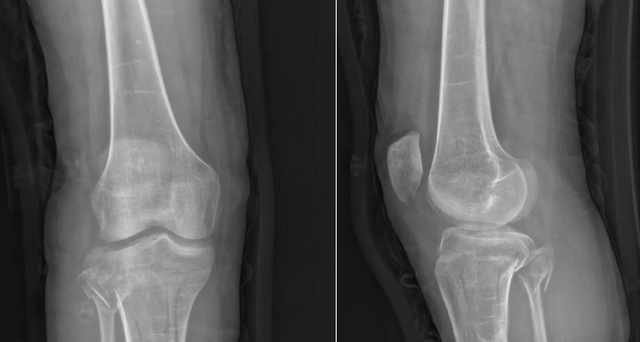

Không lâu trước đây, A Lệ nhập viện tại khoa Chấn thương chỉnh hình, Bệnh viện Đa khoa số 2 Phúc Châu do gãy xương ống chân. Kết quả chụp X-quang khiến các bác sĩ không khỏi giật mình: bộ xương của một cô gái đôi mươi lại loãng và mỏng manh chẳng khác nào người ngoài 60 tuổi. Ngay lập tức, các chuyên gia xương khớp được mời hội chẩn.

Qua thăm khám, bác sĩ ghi nhận ngoài tiền sử gãy xương nhiều lần, A Lệ còn có vóc dáng thấp bé chưa đến 1m50, răng mọc thưa và dễ sâu, phần tròng mắt lộ màu xanh nhạt. Tất cả dấu hiệu gợi ý đến một bệnh lý di truyền hiếm gặp bệnh tạo xương bất toàn hay dân gian vẫn gọi là “bệnh xương thủy tinh”.

Các bác sĩ quyết định cho hai cha con làm xét nghiệm gen. Kết quả xác nhận cả hai đều mang đột biến ở gen COL1A1, nguyên nhân trực tiếp dẫn đến tình trạng tạo xương bất toàn. Đây là bệnh di truyền hiếm, khiến quá trình tổng hợp collagen bị rối loạn, làm xương trở nên cực kỳ dễ gãy dù chỉ chịu một tác động nhỏ. Ngoài xương yếu, bệnh nhân còn thường kèm vóc dáng thấp bé, răng dễ hỏng, mắt có màu xanh bất thường.